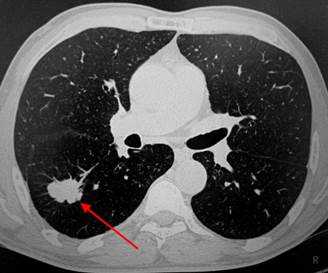

2) Плоскоклеточный неороговевающий рак - часто встречающийся вариант - до 35% всех случаев образований легких. Характеризуется наилучшим прогнозом, редко метастазирует. Примерно в 65% развивается в одном из центральных бронхов и обуславливает картину ателектаза на КТ и рентгеновских снимках, в 35% развивается в периферических бронхах и выглядит как солидный единичный узел, часто с полостью распада в центре, похожий на абсцесс.

У пациента был выявлен раковый узел в 6 сегменте нижней доли слева. После резекции путем гистологического исследования верифицирован плоскоклеточный рак легкого. Томография в данном случае не дала типичную картину злокачественного новообразования.

Типичный периферический рак легкого (аденокарцинома) на МСКТ. Справа в 6 сегменте легкого выявлен плотный мягкотканный узел со спикулами, деформирующий и подтягивающий к себе междолевую плевру.